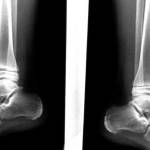

Начать лечение нельзя без проведения рентгенографического исследования, для этого назначается рентген голеностопного сустава.

После получения рентгеновского снимка, врач хорошо видит контуры связок и состояние голеностопного сустава. Таким образом, врач ставит диагноз и сразу назначает лечебный комплекс.

Врач, ставя диагноз, не должен опираться только на внешние признаки перелома. Для точной постановки диагноза он обязательно должен направить пострадавшего на рентген, причем рентгеновский снимок нужно делать в двух проекциях – сбоку и спереди ноги. Если позволяет техническое оснащение больницы, то не помешает сделать и компьютерную томографию, чтобы получить трехстороннее изображение поврежденного сустава.

- Рентгенография: стандартный метод диагностики переломов любого типа и локализации, для правильной оценки повреждения выполняется с захватом дистального и проксимального суставов от места повреждения;

— снимок кости выполняется в переднем и боковой проекции;

Для подтверждения первого медицинского заключения назначают рентгенологическое обследование.

Через 15 минут бывает готов снимок, с помощью которого доктор по контурам связок голеностопа ставит заключительный диагноз, в соответствии с ним и назначается лечение.

Основным методом диагностики перелома является рентгенологическое исследование. Больному делается снимок в стандартных двух проекциях: прямой и боковой. В самых сложных случаях визуализировать голеностопный сустав в трех проекциях помогает компьютерная томография.